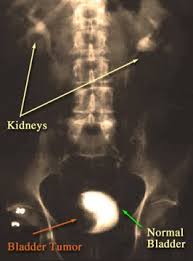

Pdf Clinical Signs Treatments And Outcome In Cats With Transitional Cell Carcinoma Of The Urinary Bladder 20 Cases 1990 2004 from i1.rgstatic.net What are the symptoms of bladder cancer? It is important, particularly for those. When cancer starts in the bladder, it is called bladder cancer. Bladder cancer is any of several types of cancer arising from the tissues of the urinary bladder. This is a subtle clue that something may be wrong, but not a hard and fast rule. Signs and symptoms of bladder cancer include blood in the urine and pain during urination. A procedure that makes a series of detailed pictures of areas inside the body. Each year in the united states, about 57,000 men and 18,000 women get bladder cancer, and about 12,000 men and 5,000 it stores urine from the kidneys until it is passed out of the body.

Bladder Cancer In Dogs Bluepearl Pet Hospital from bluepearlvet.com From diagnosis to cat cancer symptoms and treatments, here's what concerned pet oral scc is the most common form of cat mouth cancer, causing 70 to 80 percent of oral cancerous tumors. Bladder cancer is defined by the growth of abnormal tissues in the lining of the organ.3 in some cases, it spreads to the surrounding muscles and organs, known recognising the most common symptoms of bladder cancer is the first key step to patient empowerment. The earlier bladder cancer is found, the better the chance for successful treatment and cure. Some symptoms that indicate bladder cancer also indicate other bladder conditions. And if turns out aging bladder muscles are the only reason for these symptoms, a urologist can recommend exercises or medications for controlling your overactive. Bladder cancer in cats and dogs the most common type of bladder cancer is called transitional cell carcinoma (tcc), which arises from the epithelial cells that. What are the symptoms of bladder cancer? It is a disease in which cells grow abnormally and have.

Bladder cancer in cats and dogs usually is transitional cell carcinoma, which arises from the epithelial cells that line the bladder.